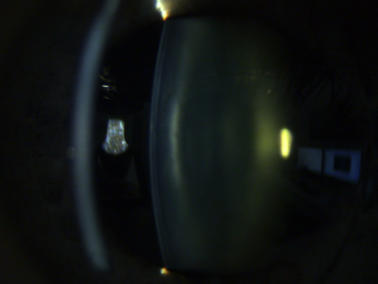

Katarakt („Grauer Star“)

Eine Katarakt (links) verursacht ein unscharfes Bild durch vermehrte Lichtstreuung. Ein Linsen - tausch (rechts) korrigiert den Abbildungsfehler.

Eine Katarakt (links) verursacht ein unscharfes Bild durch vermehrte Lichtstreuung. Ein Linsentausch (rechts)  korrigiert den Abbildungsfehler.